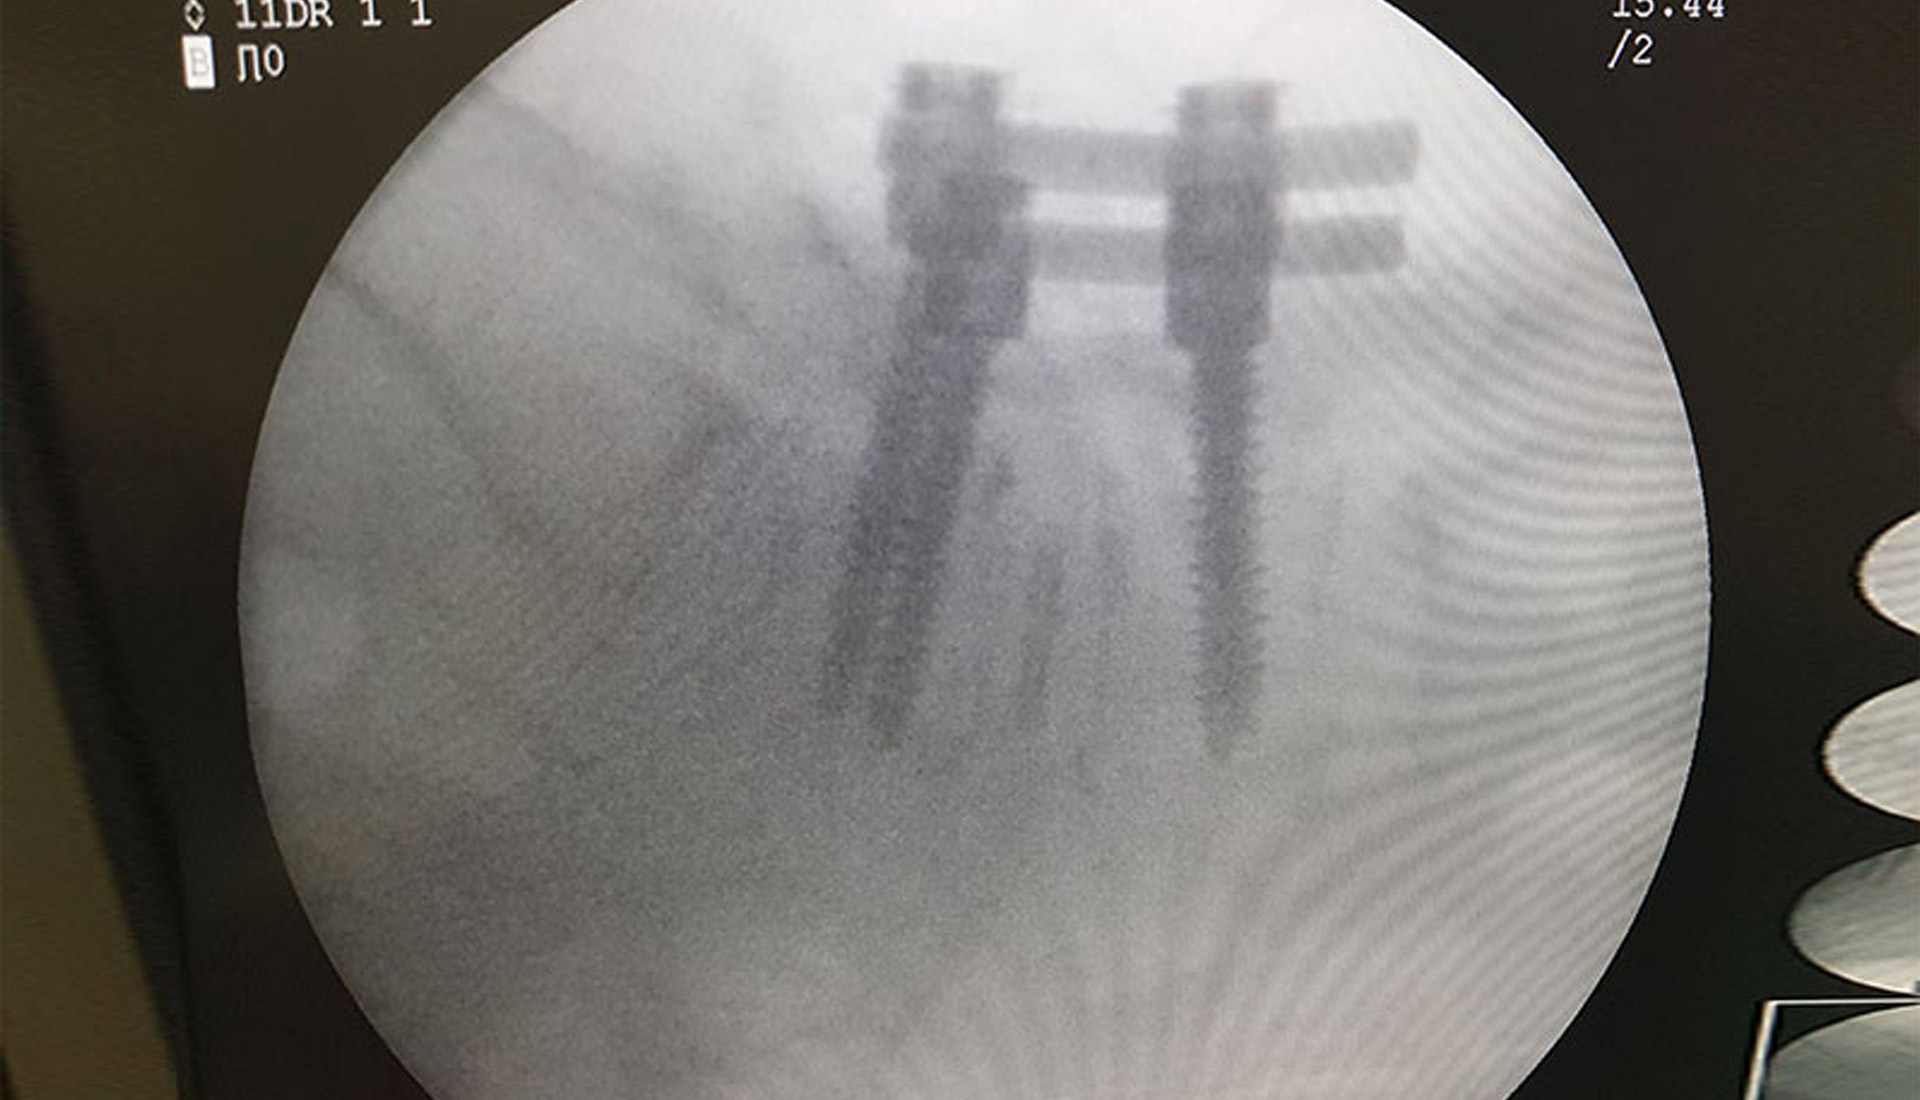

• Cerrahi : Spinal stenoz hastaların çoğunda cerrahi dışı tedaviler sonuç vermez. İyi seçilmiş hastalarda cerrahi müdahale sinirlere olan baskıyı ortadan kaldırarak hastanın normal bir hayat sürmesine yardımcı olur.